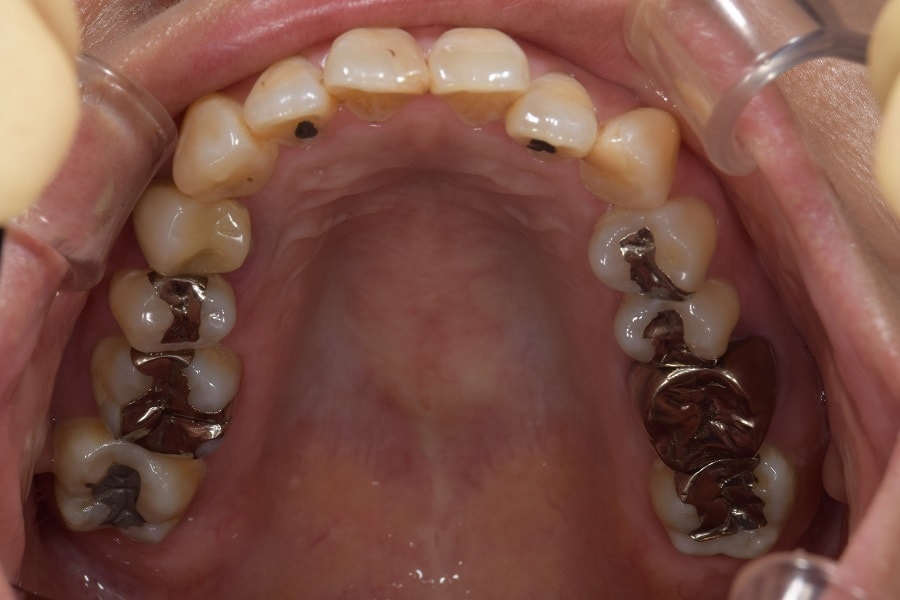

治療前

インプラント治療例

初めて来られた時は、ハブラシの状態が悪く、歯茎が腫れていたり、その他さまざまな問題もあり、とてもインプラントができる状態ではありませんでした。

治療後

インプラントは虫歯にはなりませんが、お口の中が清潔な状態に保てていなければ、自分の歯と同じように、歯周病にはかかってしまいます。そのため、当院ではご自身で歯ブラシを適切に当てることが出来て、お口の中を清潔に保つことが出来たり、歯茎の状態が整うまでインプラント治療を行うことはありません。お口の中が歯周病にかかったままの状態でインプラントをするとどうなるか・・・容易に想像がつくかと思います。